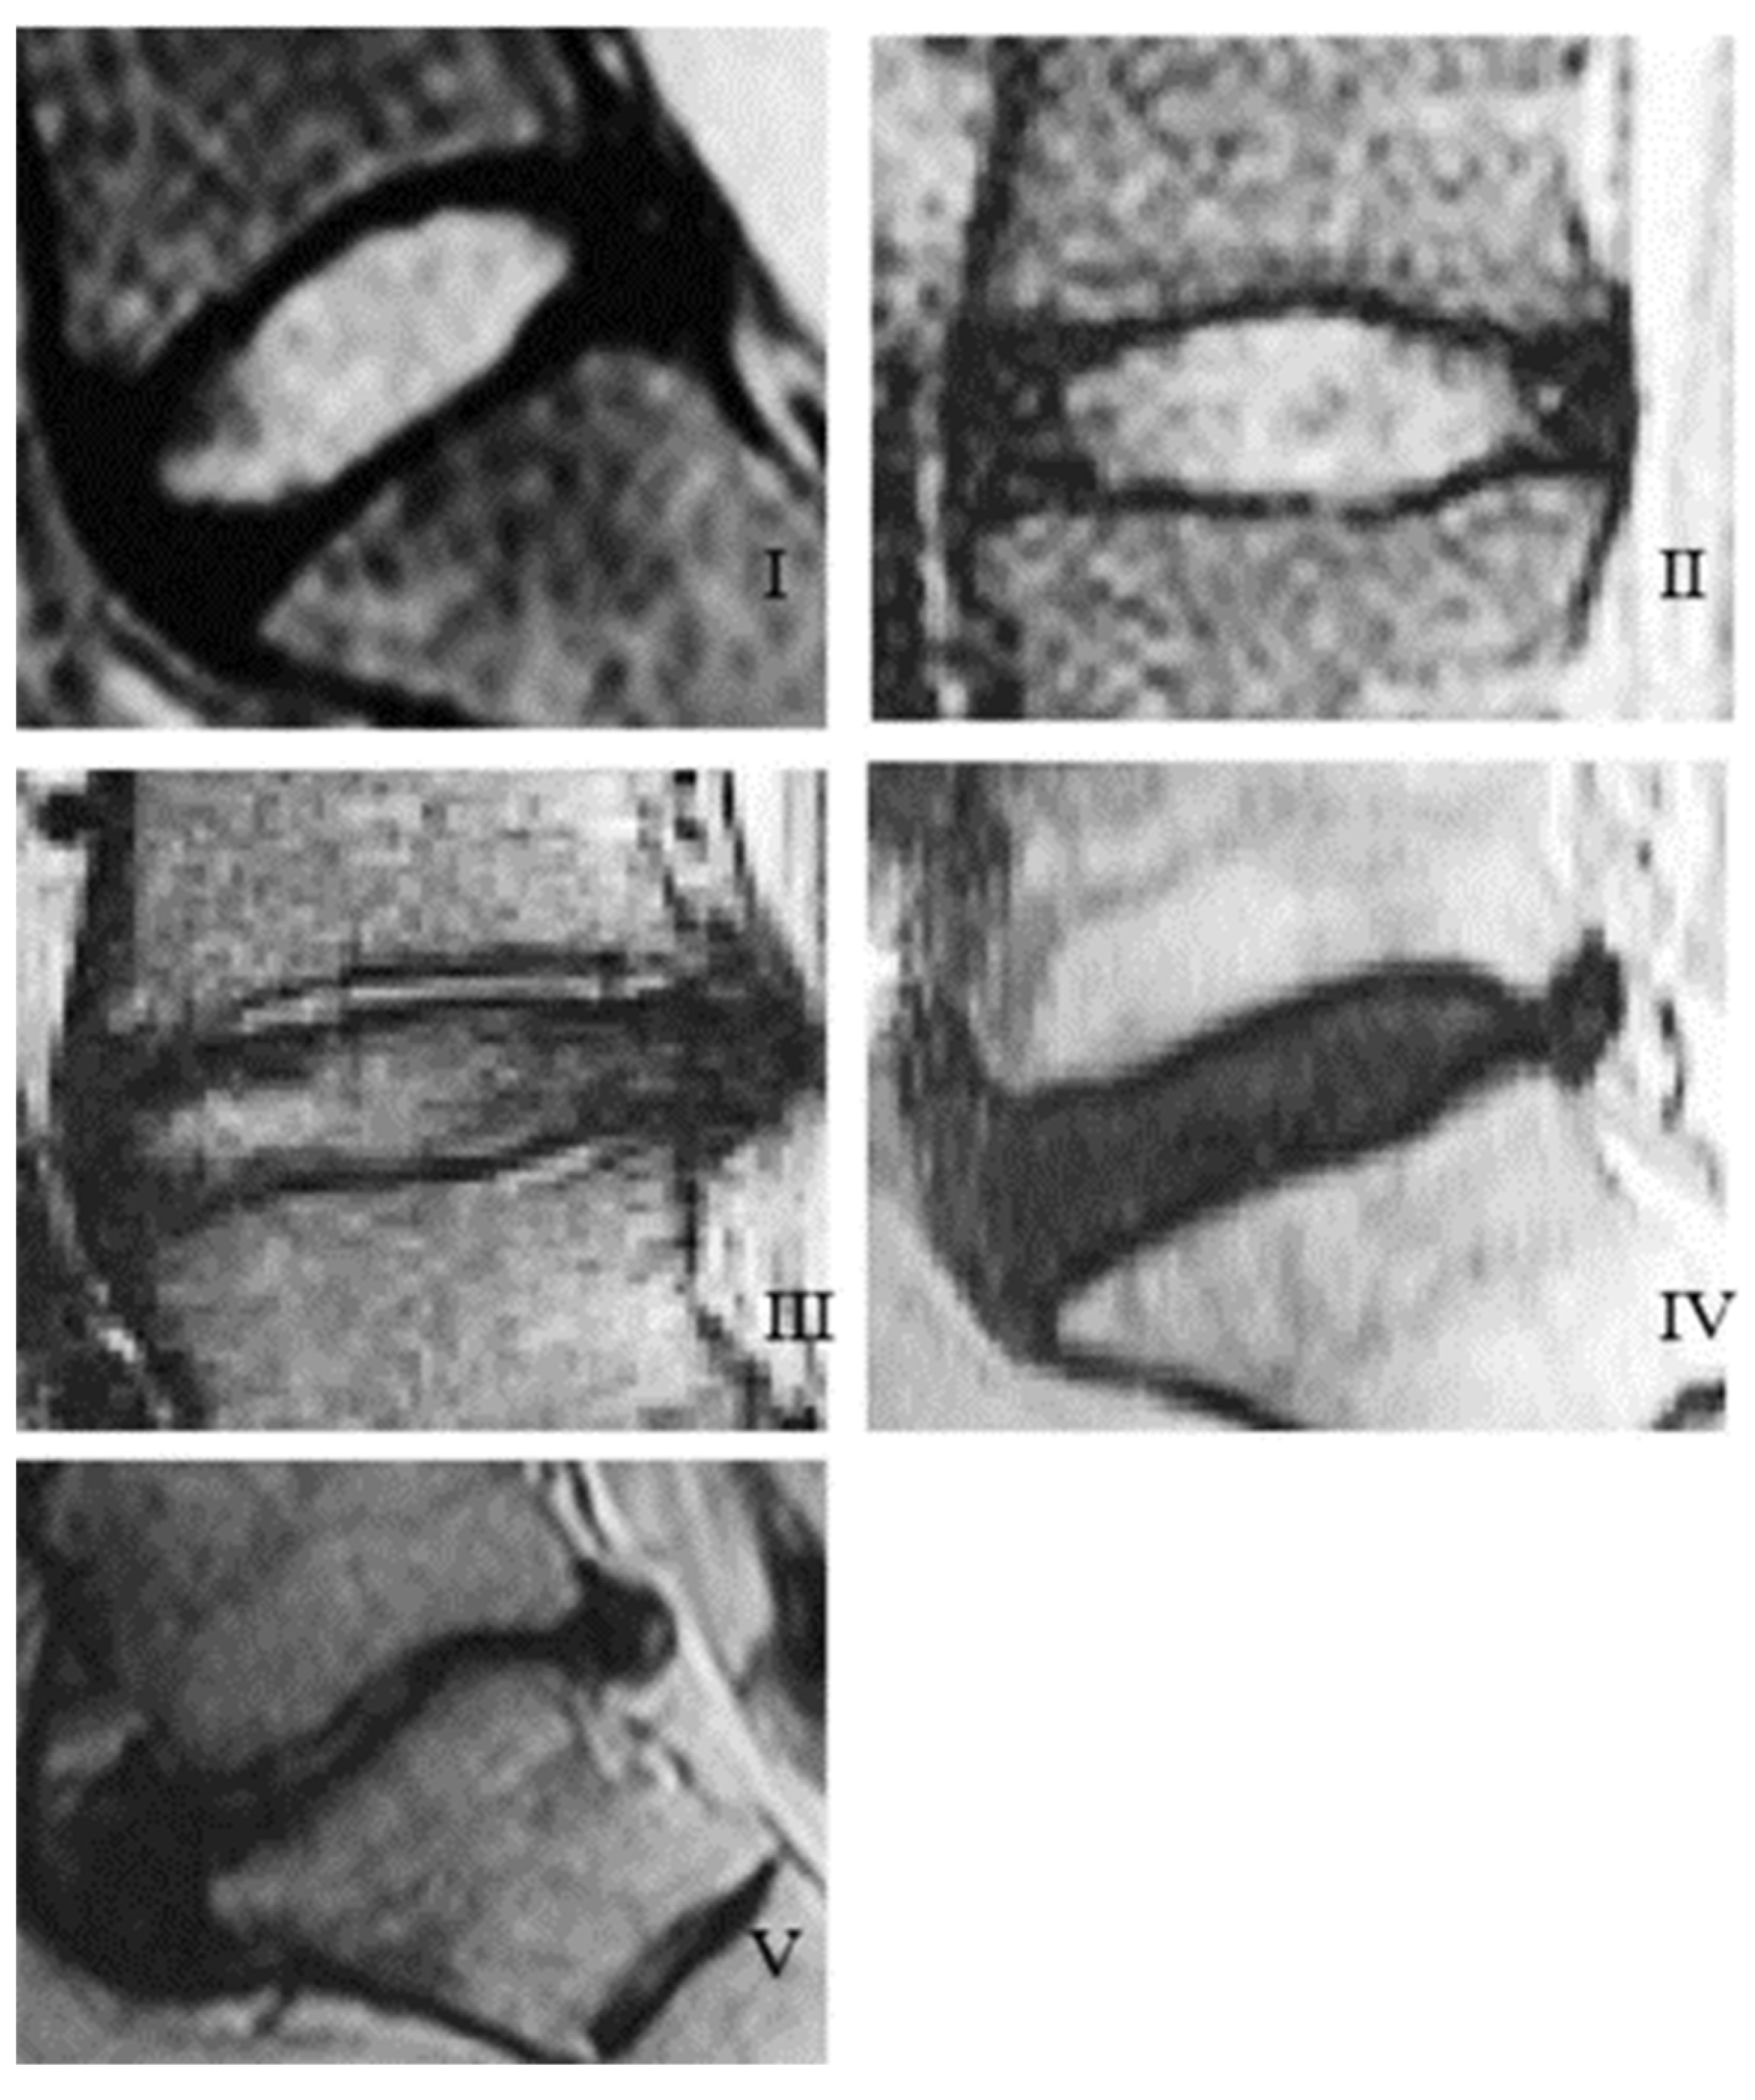

| Grade | Structure | Distinction of Nucleus and Annulus | Signal Intensity | Height of Intervertebral Disc |

|---|---|---|---|---|

| I | Homogenous, bright white | Clear | Hyperintense, isointense to cerebrospinal fluid | Normal |

| II | Inhomogeneous with or without horizontal bands | Clear | Hyperintense, isointense to cerebrospinal fluid | Normal |

| III | Inhomogeneous, gray | Unclear | Intermediate | Normal to slightly decreased |

| IV | Inhomogeneous, gray to black | Lost | Intermediate to hypointense | Normal to moderately decreased |

| V | Inhomogeneous, black | Lost | Hypointense | Collapsed disc space |